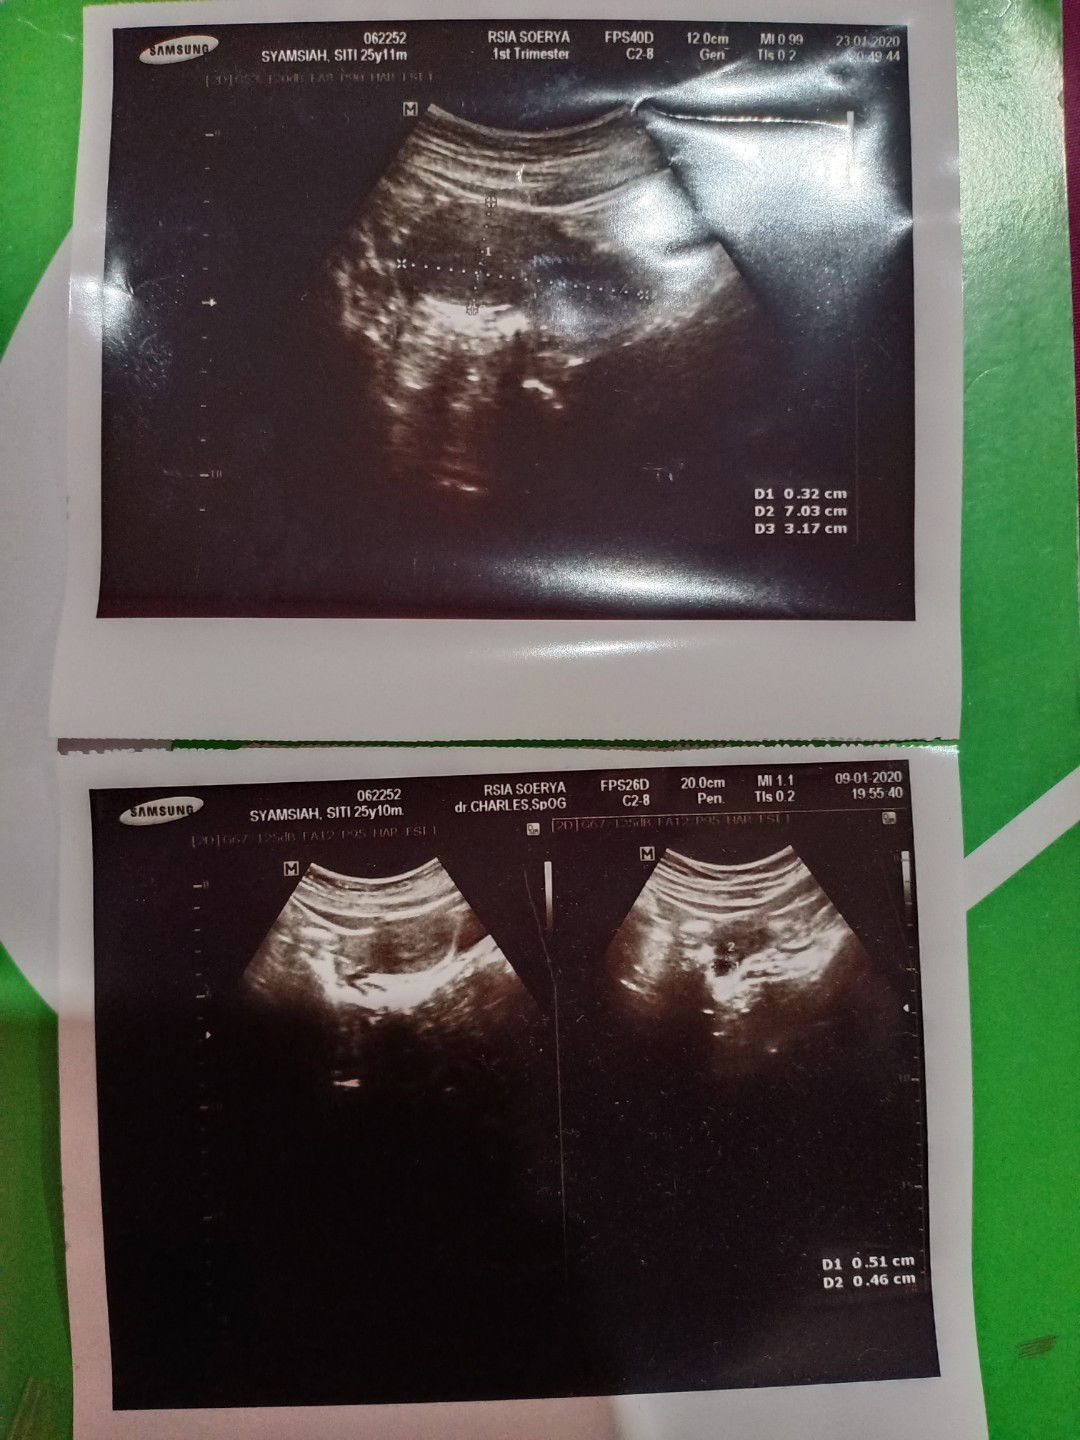

Hamil atau keguguran

Assalamualaikum Bunda, saya mau sharing pengalaman sy. Ini hasil USG terakhir saya waktu saya tespek garis 2 samar. Kata dokter saya hamil, tapi beberapa minggu kemudian sy keluar darah bund. Jadi dokter tdk bisa memastikan sy tetap hamil atau keguguran. Mungkin di antara Bunda ada yg pernah hamil dan di USG waktu 5-6 weeks, apa ini bisa dikatakan hamil ya?

Dulu saya kehamilan yg pertama usg 6w 5d udah ada janin nya bun. Mngkn setiap org masing², kadang ada yg blm kelihatan janin nya.